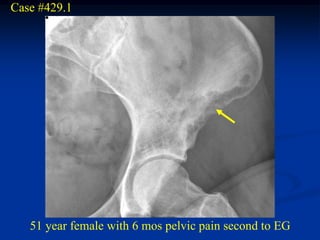

Case #429.1

51 year female with 6 mos pelvic pain second to EG

Bone scan

Axial T-2 MRI